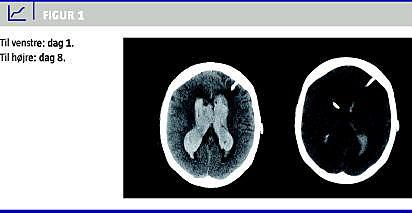

Dag 8 var mængden af blod betydeligt mindsket, og dilatationen af ventrikelsystemet var aftaget (Figur 1 ). Patienten blev på dag 22 tilbageflyttet til intensivt afsnit på lokalt sygehus til fortsat behandling. På dette tidspunkt var der et normalt dimensioneret ventrikelsystem uden blod og uden tegn på reblødning.